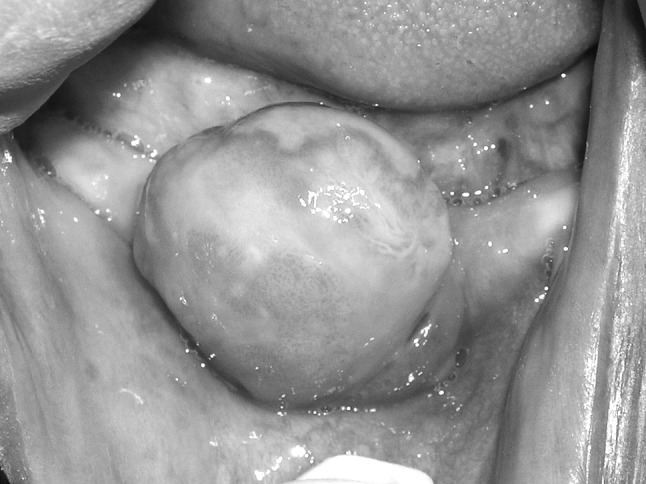

Clinical examination revealed a round, sessile, non-tender, pink mass with intermittent erythematous islands on the right anterior alveolar mucosa of her edentulous mandible (Fig. 1). It measured 2.5 cm in diameter. The growth had a broad based attachment to the surrounding mucosa, was nonfluctuant and had a firm, rubbery consistency. It did not blanch with pressure.

Fig. 1.

Growth in right edentulous mandibular alveolar ridge